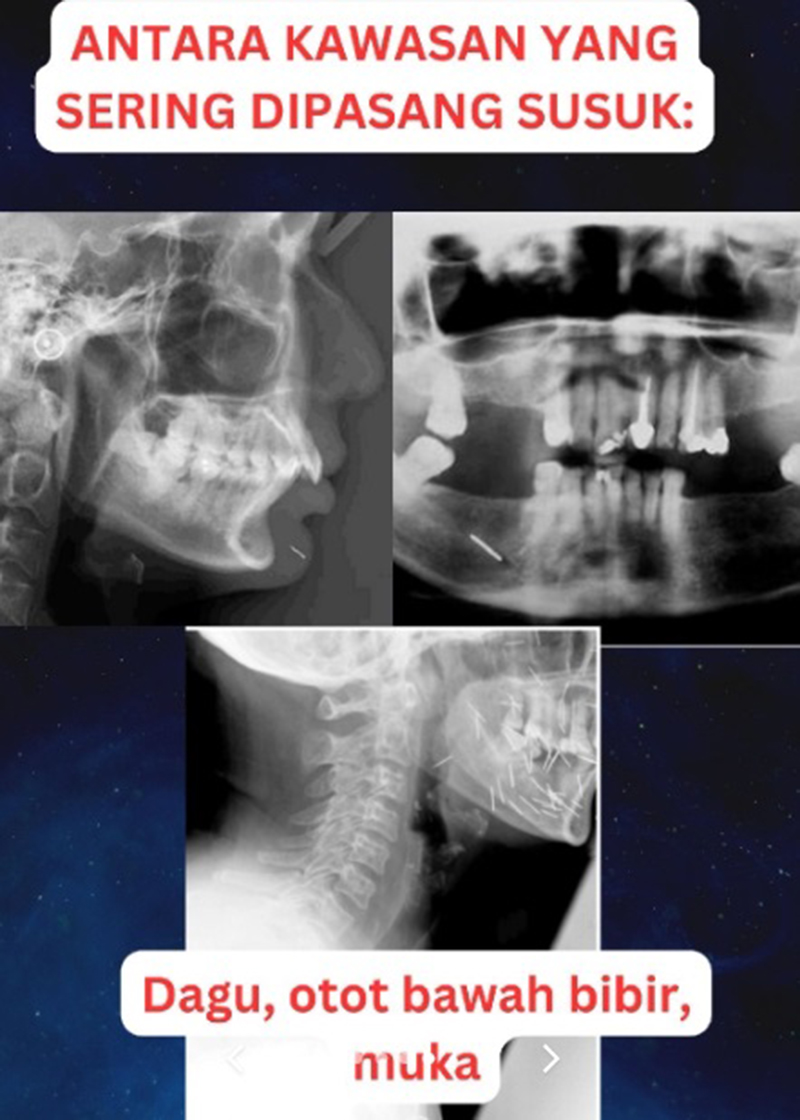

ภายหลังจากการตรวจร่างกาย ตรวจเลือด ทำซีทีสแกน และเอกซเรย์ ทางทีมแพทย์ต่างก็ประหลาดใจไม่น้อยเมื่อพบว่า มีเข็มฝังอยู่ทั่วร่างกายของเธอ กระจายอยู่ 4 ส่วน ได้แก่ บริเวณดวงตา ใบหน้า ลำคอ และหน้าอก โดยเข็มดังกล่าวนี้ เป็นเข็มบาง ๆ ทำด้วยทองหรือวัสดุโลหะอื่น ๆ เรียกกันว่า ซูสุก (Susuk) หรือเข็มเสน่ห์ ตามความเชื่อท้องถิ่นที่ได้รับอิทธิพลมาจากอินโดนีเซีย ผู้หญิงหลายคนเชื่อว่าการสอดเข็มเล็ก ๆ นี้ เข้าไปในส่วนต่าง ๆ ของร่างกายจะช่วยให้ผู้คนเกิดความลุ่มหลง ทำอะไรก็จะสำเร็จดั่งที่ใจปรารถนา